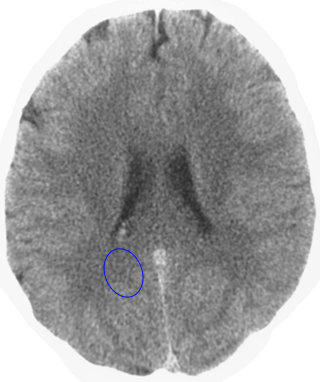

Which is the brain relais that is shown here? 25 Questions each cycle, try more!

Question 1 of 25

Middle ear mucosa left

Rectal mucosa

Coronary arteries, aortic arch, carotid arteries, bradycardia, penile sensitivity, clitoral sensitivity

Liver

Left hemispheres of the retinas

Lesser curvature of the stomach, mucosa of the bile ducts, pancreatic ducts, bulb of the duodenum